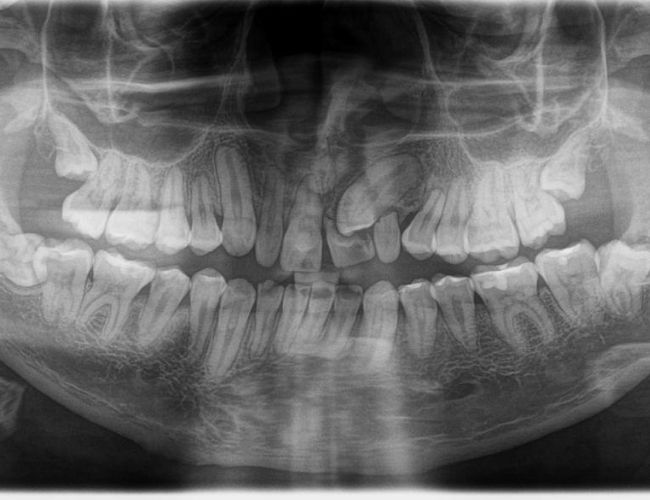

La cirugía oral es una rama de la odontología que se ocupa de tratar quirúrgicamente enfermedades, lesiones y problemas bucodentales complejos que no pueden resolverse con tratamientos convencionales.

Los procedimientos más comunes incluyen la extracción de muelas del juicio (terceros molares) y dientes retenidos, así como la eliminación de quistes y otros problemas en la cavidad bucal.

- Necesitas extraer tus muelas del juicio debido a molestias, falta de espacio o crecimiento anómalo.

- Tienes dientes retenidos o que no han erupcionado correctamente y requieren intervención quirúrgica.

Las muelas del juicio suelen extraerse si causan dolor, están retenidas, no tienen suficiente espacio para erupcionar o representan un riesgo para la alineación de otros dientes.